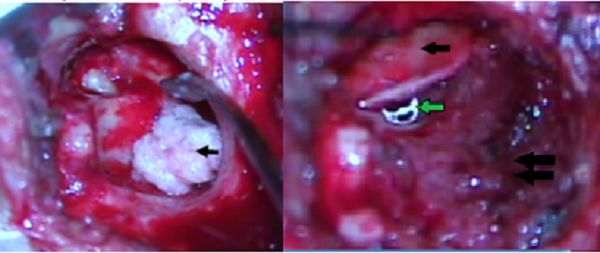

Figure 2.

A. Open mastoidectomy with immediate reconstruction. Mastoid obliteration and reconstruction of the posterior wall of the EAC using powdered bone (arrow). B. Open mastoidectomy with immediate reconstruction. Cartilage graft for tympanoplasty (black arrow), titanium TORP prosthesis below the graft (green arrow), posterosuperior wall of the EAC reconstructed with powdered bone (double black arrow)